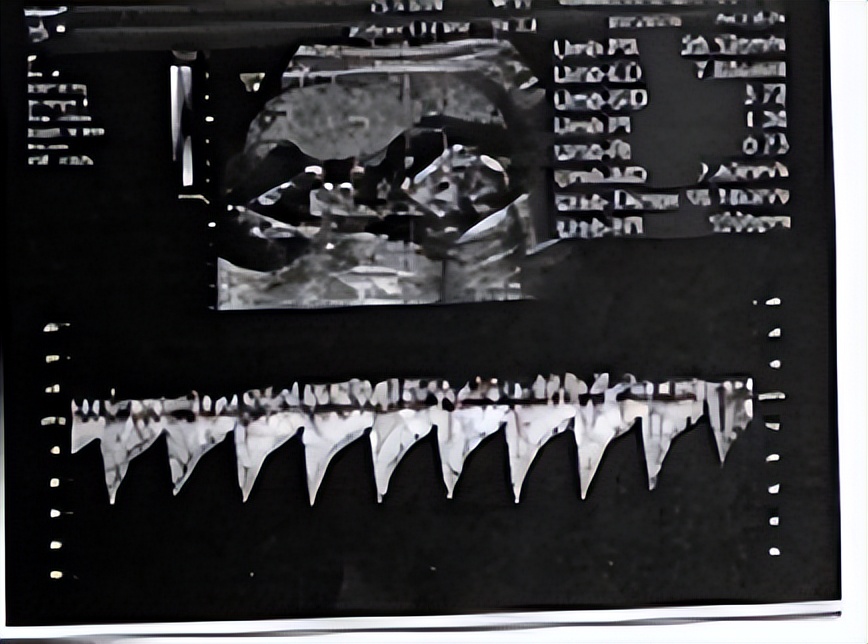

【疾病类型】孕17+1周先兆流产

患者是去年到我院进行胚胎移植,移植冻胚2枚,存活1枚。怀孕期间到我院定期产检,孕13周时发现血压升高,最高到165/101mmHg,遂予以拉贝洛尔降压治疗,以及拜阿司匹林改善循环、补钙等。入院前3小时,患者自觉肚子疼痛伴少量阴道流血,遂急诊入院,途中阴道流血症状渐渐消失,但腹痛尚存。

患者产科检查结果如下:宫高脐下2指,胎心率150次/分,无宫缩,无阴道流血无活动性阴道流水。阴道检查结果显示:阴道通畅,内有少量暗红色血液,宫颈非常大,光滑。骨盆测量:耻骨弓不低,侧骨盆不内聚,出口横径9cm。入院时测得指血糖5.7mmol/L,血压117/82mmHg。患者既往在我院门诊进行常规产检时,未检出明显异常。

本次患者因突发腹痛伴阴道流血入院,腹痛发作无规律,考虑先兆流产可能性大,由于先兆流产如不尽快处理可能转变为难免流产,而目前患者血糖、血压控制良好,不需处理,遂予以患者诊断性治疗:硫酸镁,改善胎盘循环功能;间苯三酚,解痉,抑制宫缩;黄体酮保胎等对症支持治疗。

予以治疗后,患者腹痛症状渐渐缓解,无明显腹痛、阴道流血及活动性流液,未出现特殊不适,提示保胎成功,治疗有效,证明患者确实为先兆流产。目前患者一般情况可,可以出院,嘱咐患者出院后需要注意休息,尽量避免剧烈运动, 避免受到外界刺激的影响,保持情绪稳定,心情愉悦,按时服用药物,并且1周后来产科门诊复查B超。

经过给予给予硫酸镁,改善胎盘循环功能;间苯三酚,解痉,抑制宫缩;黄体酮保胎等对症支持治疗。目前患者一般情况尚可,未诉特殊不适,查体,神清,精神均尚可,心肺未及明显异常,妊娠腹型,胎心:150次/分,双下肢无水肿。治疗效果:治愈。患者要求出院,予以出院。嘱患者出院后注意休息,避免剧烈运动,1周后来产科门诊复查B超。